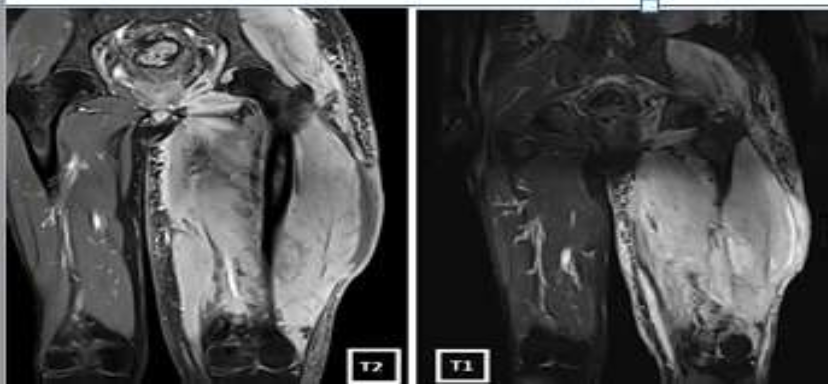

He underwent a pelvic MRI that documented altered signal intensity (high signal on T2/STIR and low signal on T1) in left psoas, iliacus, obturator internus, pyriformis, gluteal and the left thigh muscles. (Figure 2).

Figure 2a: Pelvic MRI showing altered signal intensity in the left thigh muscles

Because of the routine use of CT scan in oncologic staging most skeletal muscle metastases are detected on CT scan, however MRI is considered superior to CT scanning for detecting and characterizing muscle abnormalities. [1,9] Muscle metastatic lesions frequently reveal isointense signal to muscle, with ill-defined margins on T1-weighted MRI, and heterogeneous signal intensity with well-defined margins, in addition to peritumoral edema on T2-weighted images.[3]